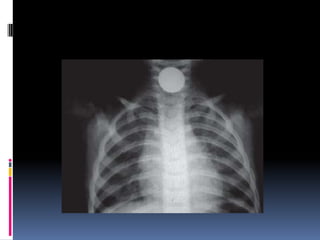

 Estudios Radiológicos.-

 Rx. DeTórax AP. y Oblicuo.

Localización • Inmediatamente pordebajo del músculo cricofaringeo. • Encima de la unión gastroesofágica. • En los relieves que establecen el cayado de la aorta y el bronquio principal izquierdo.

Síntomas  Disfagia ydolor supraesternal - Si el objeto es voluminoso puede producir excesiva y dificultad respiratoria.  Dolor retroesternal con irradiación a la espalda (localización en tercio medio del esófago.  Regurgitación( localización tercio inerior)

Diagnostico  Estudios Radiológicos.- Rx. Simple de Esófago Cervical vista Lateral.  Fluoroscopía de Esófago con mota de algodón  Embebida en bario.  Rx. DeTórax AP. y Oblicuo.  Exploración Endoscópica.